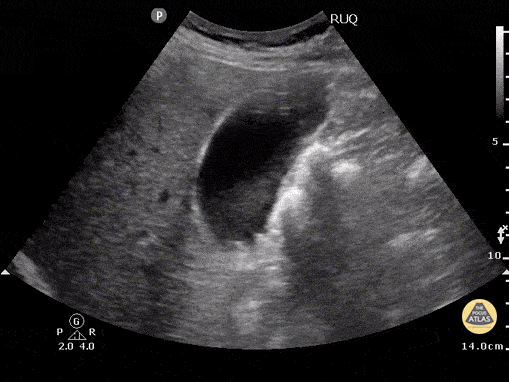

Biliary - Cholelithiasis - Neck Stones

This patient w/o cholecystitis clearly demonstrates cholelithiasis. A 2002 study showed that ER doctors can diagnose gallstones with a sensitivity of 88% and specificity 96% with POCUS. Gallstones can be identified by hypoechoic "shadowing" behind hyperechoic stones. If there isn't shadowing, hyperechoic structures could represent polyps or sludge. In this image the stones are resting mainly in the neck of the gallbladder. Kendall JL, Shimp RJ. Performance and interpretation of focused right upper quadrant ultrasound by emergency physicians. J Emerg. Med. 2001; 21(1):7-13 Submitted by Justin Bowra MBBS, FACEM, CCPU Emergency Physician, RNSH et al.